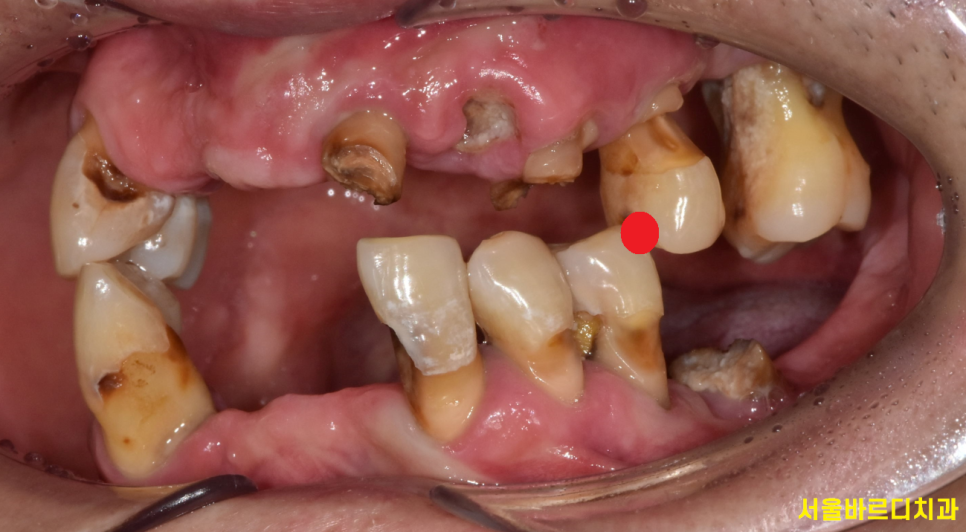

전반적으로 치아가 망가진 경우

치아의 높이 역시 무너진 경우가 많습니다.

오늘 환자분도 씹는 부위가 딱 1부분이었습니다.

치아 높이가 무너지면

얼굴 형태도 변화합니다.

한마디로 나이가 들어보이는 인상을 가질 수 있는데요.

무너진 높이를 정상으로 회복하기 위해서는

어금니로 높이를 만들어주고

앞니를 제작해주는 편이죠~